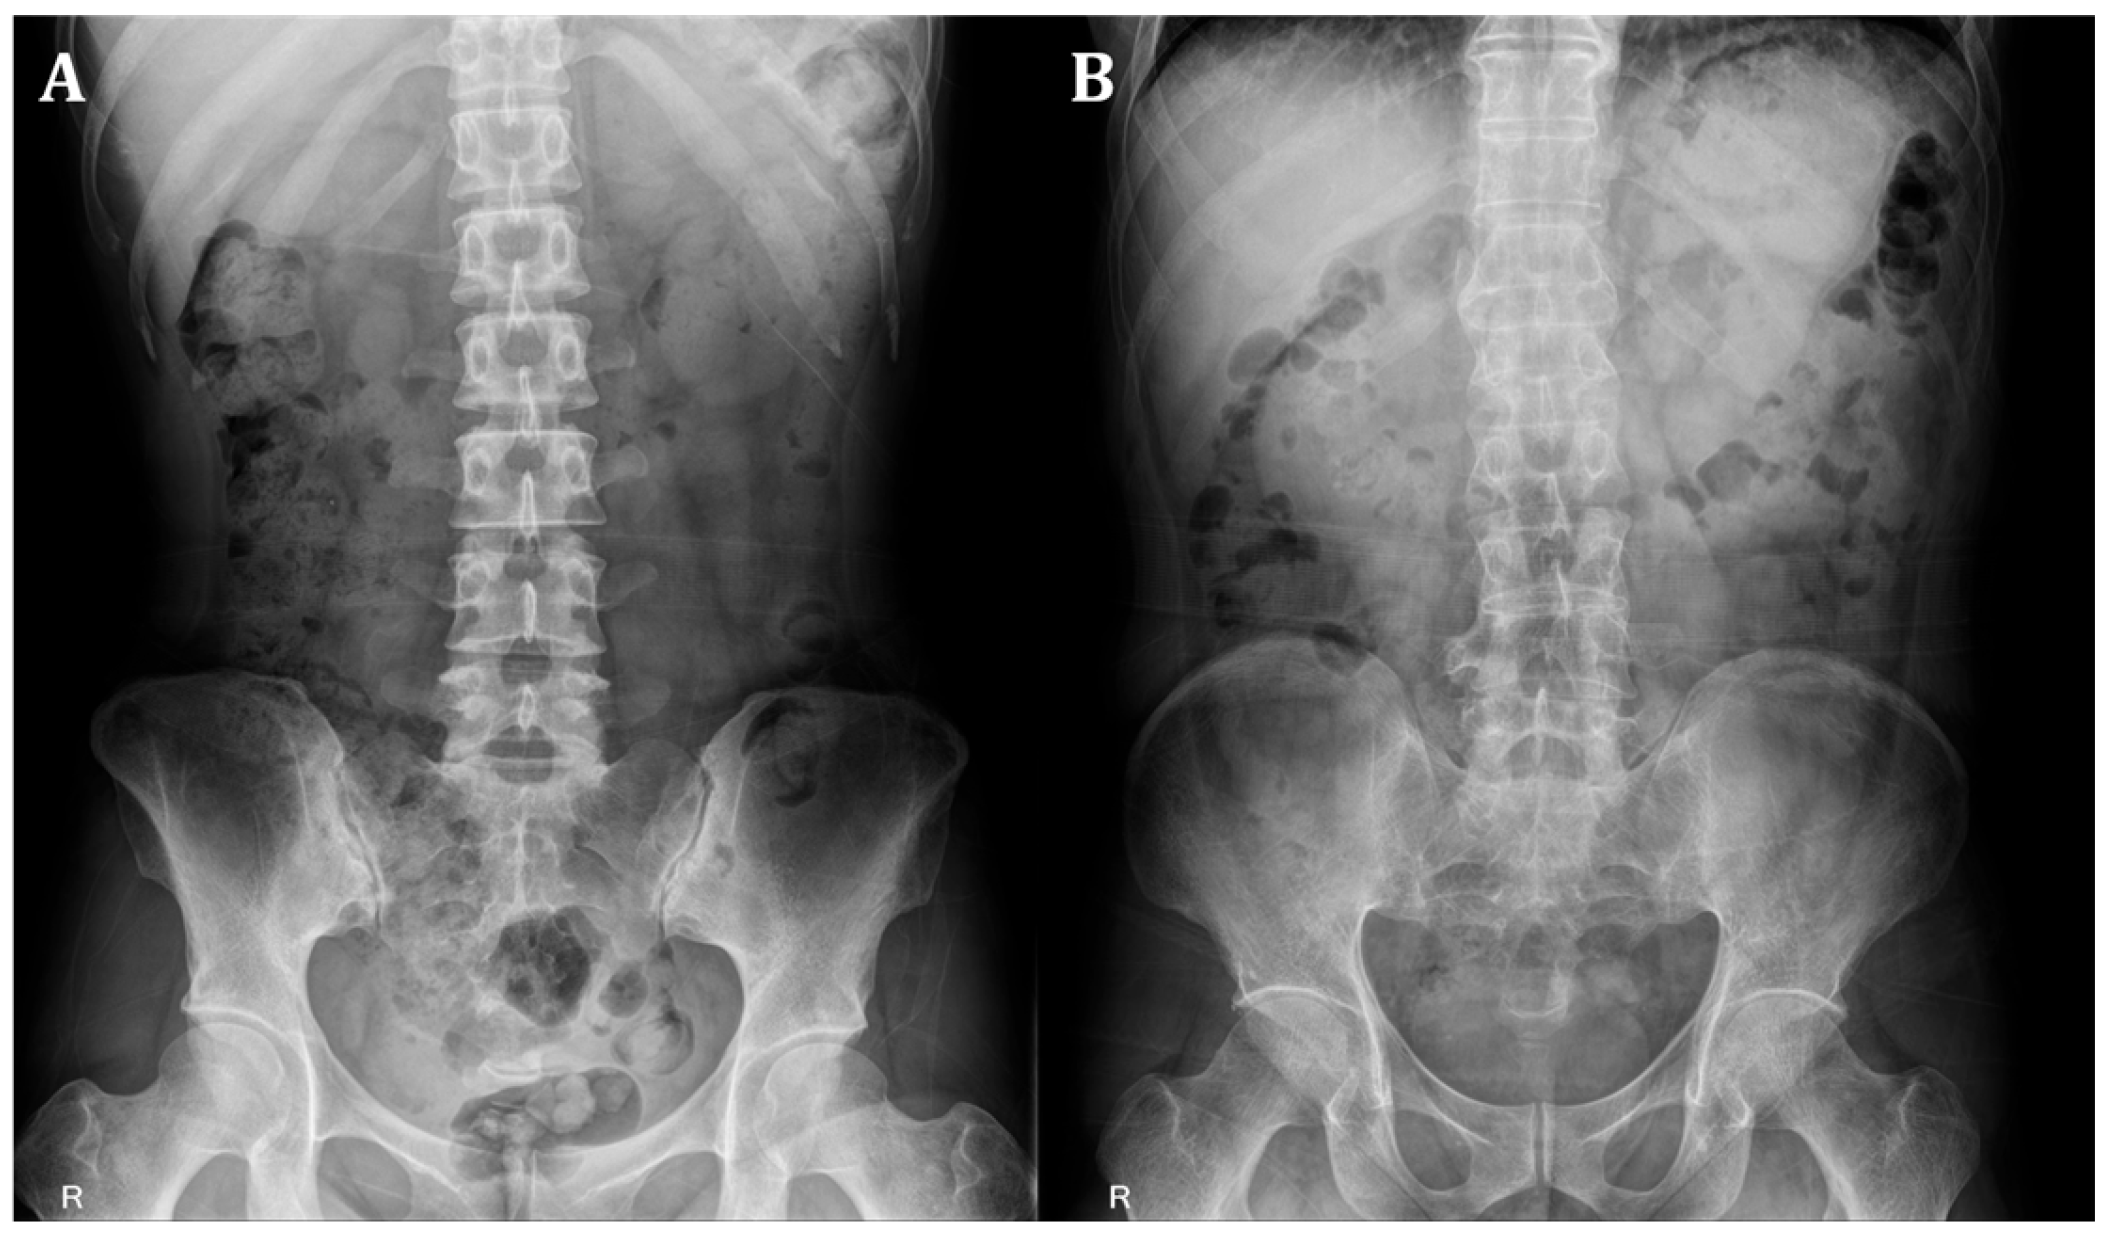

From each patient’s pelvic AP radiograph, initial ROI images were extracted and standardized to a size of 600 (height) × 300 (width) pixels. The ROI images included the left and right SIJs. Two separate ROI images containing the left or right SIJ portions were extracted from the initial ROI images of size 2865 (height) × 2344 (width) pixels. These left and right SIJ ROI images were used for training the models to detect sacroiliitis. Figure 1 provides representative examples of absence and presence sacroiliitis on bilateral SIJs.

Figure 1. (A) Absence of sacroiliitis on bilateral sacroiliac joints. (B) Presence of sacroiliitis on bilateral sacroiliac joints.